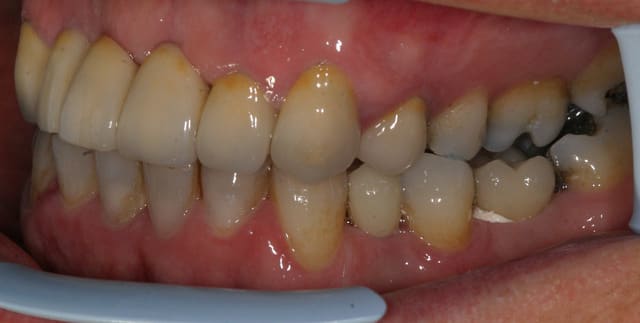

tient un boulot ou il y a un peu de tout.

bridge antérieur , car la pose d'implants nécessitait de la reconstruction trop importante, endo couronne sur les molaires mandibulaires par manque de hauteur, onlay. implants à la mandibule.

A noter les 2 PM maxillaires qui comportaient

chacune 3 canaux.